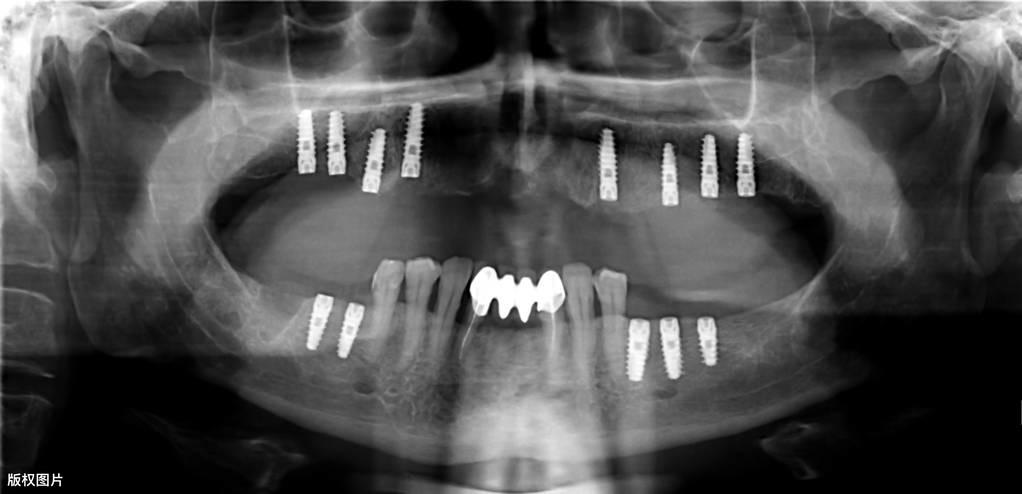

種植牙手術(shù),是門診的常規(guī)小手術(shù),它是將生物材料制成的一種人工牙根(種植體)植入到人體的頜骨內(nèi),然后在人工牙根上做上牙冠,從而恢復(fù)口腔的咀嚼功能及美觀。

種植牙的一般流程● 術(shù)前檢查:術(shù)前需要拍攝X線片、頜骨CT等,對(duì)缺失牙的部位及整個(gè)口腔狀況進(jìn)行系統(tǒng)性檢查。符合種植的適應(yīng)癥,排除禁忌癥后,根據(jù)患者的具體情況制定種植調(diào)節(jié)方案,預(yù)約種植手術(shù)時(shí)間。

● 垂直方向的骨吸收不超過種植手術(shù)完成時(shí)植入在骨內(nèi)部分長(zhǎng)度的1/3(采用標(biāo)準(zhǔn)投照方法X光片顯示)。醫(yī)學(xué)教育|網(wǎng)搜集橫行骨吸收不超過1/3, 種植體不松動(dòng)。

● 放射學(xué)檢查,種植體周圍骨界面無透影區(qū)。